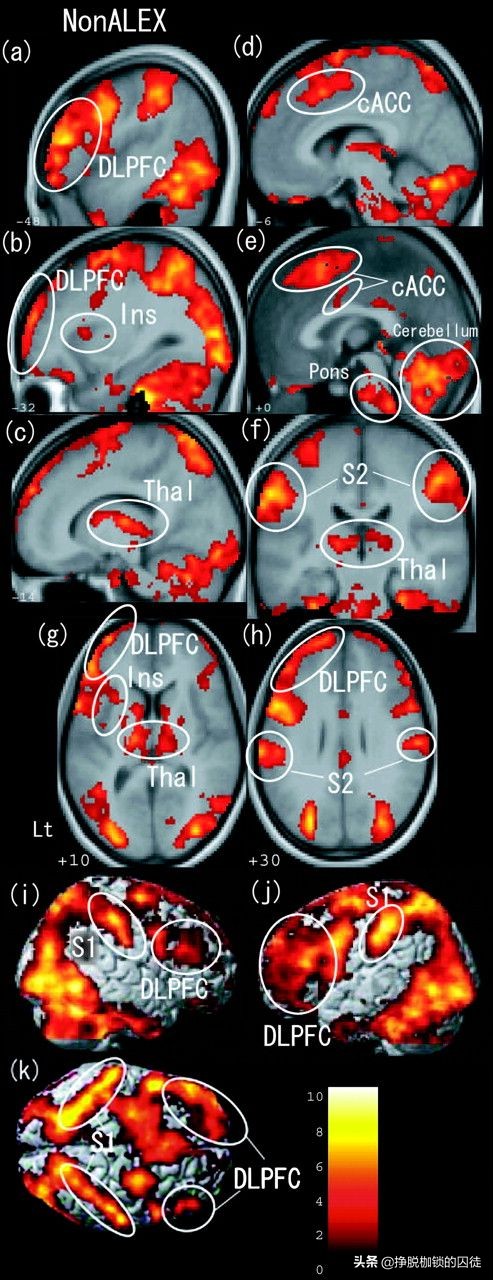

比如下图所示,一个人看到别人疼痛时相应的脑区活性的增加(白圈圈起区域,图中,CACC标识的就是前扣带回):

这种现象已经被很多研究重复证实,是得到广泛承认的科学现象。

这足以说明,看到别人疼痛,自己的的确确可以真实感受到相同部位的真实的疼痛和痛苦,证明“感同身受”是具有坚实的神经学基础的。